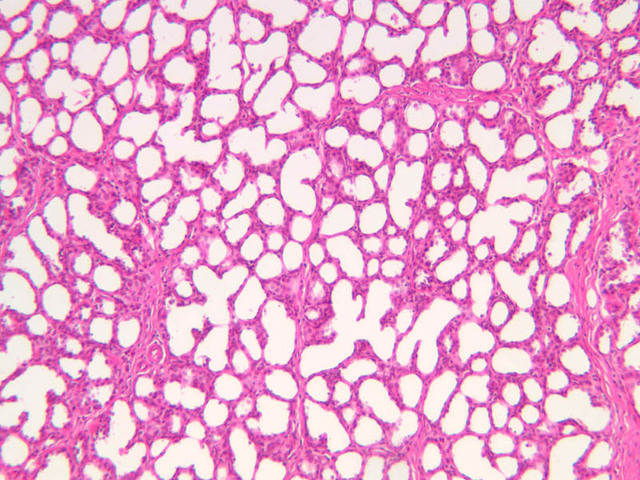

Secretory Phase

This phase occurs on days 15 to 27 and corresponds to the ovarian luteal phase characterized by rising levels of progesterone. The epithelial cells begin to secrete a mucoid fluid rich in nutrients, especially glycogen. The glands become highly coiled and folded and toward the end, very distended. The density of the stroma lessens as it becomes edematous. (slides B-99 [2.5x, 10x, 20x, 40x] [2.5x, 10x, 20x, 40x]; B-100 [1x, 2.5x] [2.5x, 10x, 20x, 40x] [2.5x, 10x, 20x, 40x])